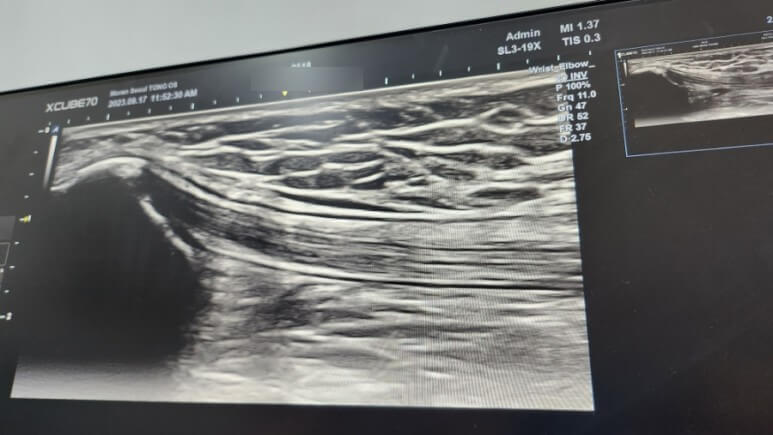

다시 누워서 초음파 촬영

그 후 초음파 촬영하며 주사 주입

주사가 잘 들어갔나 보는 영상 촬영

초음파 보면서 통증있던 왼무릎의 염증소견받음

아프다 했더니 주사 치료 해주심

썡으로 초음파보면서 주사 쭉쭊 놔주심

여기서 끝나지 않고 주사가 잘? 들어갔는지 보는 영상도 찍음.